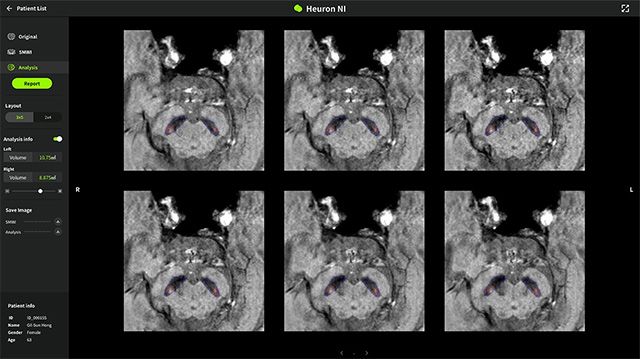

휴런NI는 MRI 기반으로 도파민 신경세포 손상의 주요 지표인 ‘나이그로좀(Nigrosome)’ 부위를 정량 분석해, 파킨슨병 관련 영상을 보다 정밀하게 시각화하는 AI 솔루션이다. 사측은 나이그로좀 부위의 부피 감소는 파킨슨병 진행과 연관된 것으로 알려졌으며, 해당 솔루션이 의료진의 영상 판독을 좀 더 용이하게 지원한다고 설명했다.